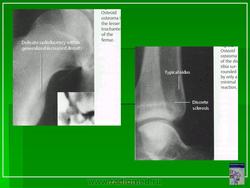

Рентгенологическая картина остеоид-остеомы весьма характерна. Рентгенологические симптомы возникают значительно позже клинических проявлений опухоли, и первым на рентгенограмме обнаруживают склероз кости. На участке поражения формируется одностороннее или муфтообразное утолщение кости в виде гиперостоза. Позднее в толще гиперостоза формируется основной отличительный признак остеоид-остеомы - ее «гнездо» в виде очага разрежения диаметром до 1 см, внутри которого могут отмечаться мелкие костные включения. Сквозь слой склерозированной ткани «гнездо» опухоли на обычных рентгенограммах не всегда дифференцируется и для ее выявления применяют лучи повышенной жесткости и томографию. Обнаружение «гнезда» необходимо для подтверждения диагноза и проведения направленного оперативного вмешательства.